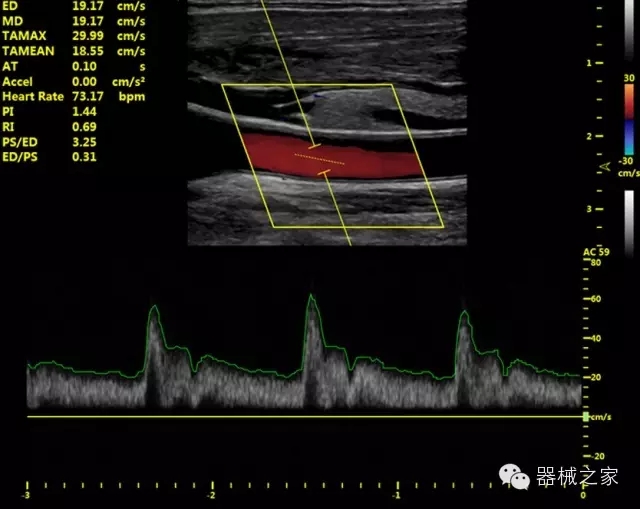

臨床圖片賞析

·獨(dú)有的HoloTM PW 實(shí)時(shí)3取樣門PW成像技術(shù),精確進(jìn)行血管診斷;

·一鍵優(yōu)化B、Color、PW,Auto Doppler自動(dòng)識別血管位置、偏轉(zhuǎn)角度等,提高工作效率;

·30°超廣角精細(xì)偏轉(zhuǎn)成像技術(shù),更優(yōu)異的頻譜圖像;